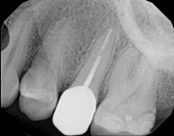

Missed canals and sclerotic orifices/canals:

Before

4-month post-opIn this situation, some would say the canals are so “calcified” that root canal treatment can’t be done; or sometimes the canal can’t be found. And because of that the tooth would need an extraction and an implant. In some instances, root canal therapy can’t be done but that does not mean the tooth is a loss. The solution is micro-apical surgery, an apicoectomy.